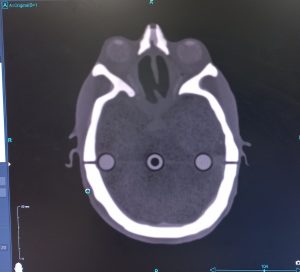

فانتوم سر و گردن

هدف از فانتوم سر و گردن، بهینه سازی و کنترل کیفی پرتو درمانی بیماران مبتلا به تومورهای سر و گردن می باشد. این فانتوم دارای بافتهای معادل بافتها و ارگانهای مختلف شامل مغز، پاروتیدها، چشم ها، عدسی ها، اعصاب بینایی، استخوانها و سینوس و حفرات هوایی بوده و جهت دوزیمتری و ارزیابی مسائل پیچیده پیرامون فرایند راه اندازی و مقایسه سیستم های طراحی درمان و تضمین کیفیت کامل سیستم از تصویربرداری CT تا تأیید دوز مناسب خواهد بود. با ارائه یک فانتوم سر و گردن با هزینه کم در مقایسه با نمونه های مشابه خارجی، بخشهای رادیوتراپی با منابع محدود می توانند جهت انجام آزمونهای ارتقای کیفیت مراحل مختلف پرتودرمانی، از این فانتوم در جهت بهینه سازی درمان با همفکری فیزیست و پزشک رادیوانکولوژی با تغییر پارامترهای مختلف اقدام نمایند.